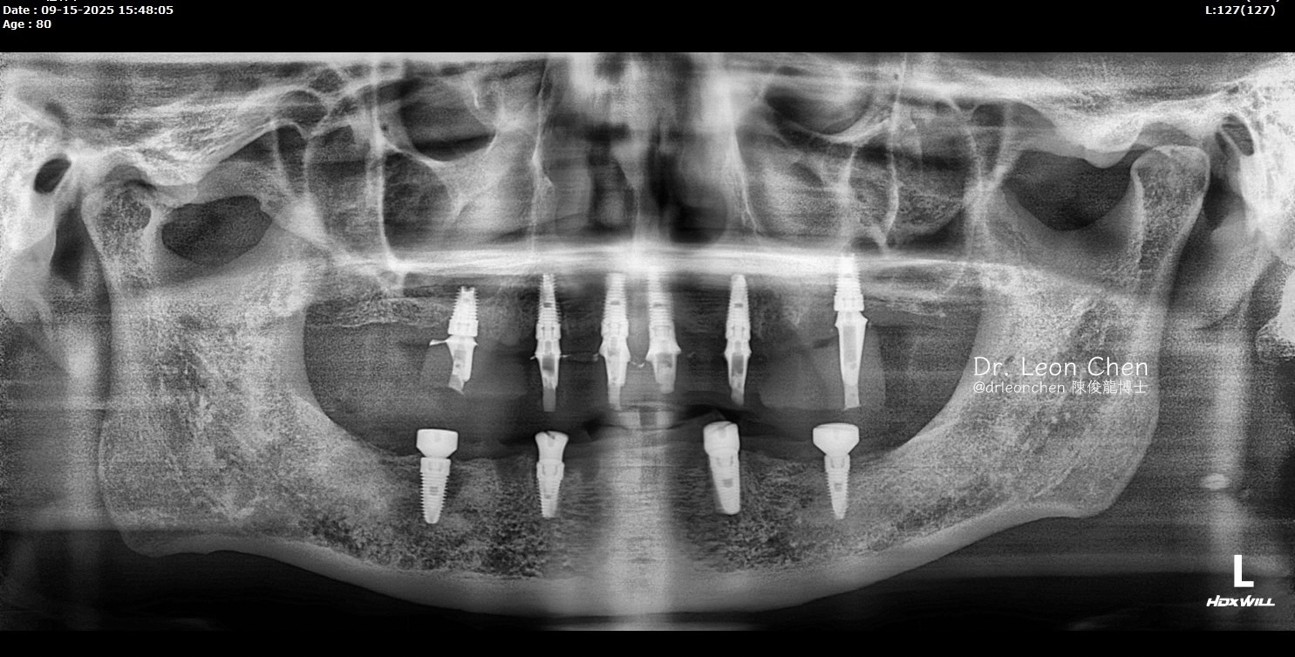

精奈創一鑽植牙系統團隊|改變80歲好朋友的決定!

有一位臨時走進診所,要做全口植牙的新病人。預約回診當天,他特地帶了小學的好朋友一起來,這位朋友也有全口植牙的需求。

病人因為對手術結果非常滿意,就推薦好友一起來找陳博士治療。

「陳俊龍博士整套 LEONS Concept 精奈創一鑽植牙」技術手術少,創傷小,恢復快!

沒有併發症;適合各類患者,不用停藥,也可以接受治療。